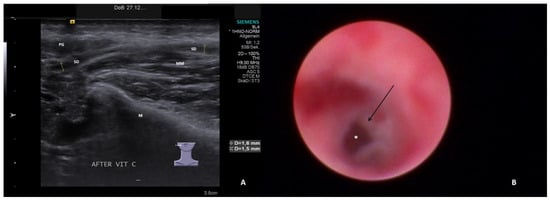

- Hypoechoic and homogeneous (no relevant loss of gland parenchyma; Figure 1A)

- Chronic sialodochitis (SD: inflammation, paleness of the duct wall, plaques, discharge; Figure 1B; Supplementary Video S1)